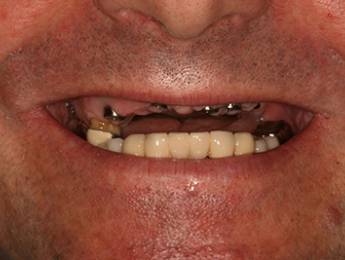

Nagymértékű fogkopás, erózió, csikorgatás a teljes rágóapparátust túlterhelve okoz reménytelennek tűnő helyzeteket.

Ebben az esetben implantátumok , koronák és hidak segítségével változtattunk a páciens fogainak érintkezésén. 6 hónapig ideiglenes hidakkal teszteltük a megváltoztatott harapási pozíciót. Ezután készültek el a végleges fix pótlások.